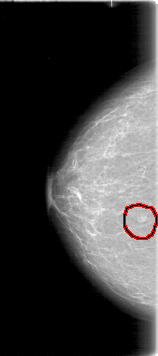

D_4009_1.LEFT_CC

RIGHT_CC LINES 5326 PIXELS_PER_LINE 2356 BITS_PER_PIXEL 12 RESOLUTION 43.5 OVERLAY

FILE: D_4009_1.RIGHT_CC.OVERLAY

TOTAL_ABNORMALITIES 1

ABNORMALITY 1

LESION_TYPE MASS SHAPE LOBULATED MARGINS OBSCURED

ASSESSMENT 0

SUBTLETY 4

PATHOLOGY BENIGN

TOTAL_OUTLINES 1

BOUNDARY